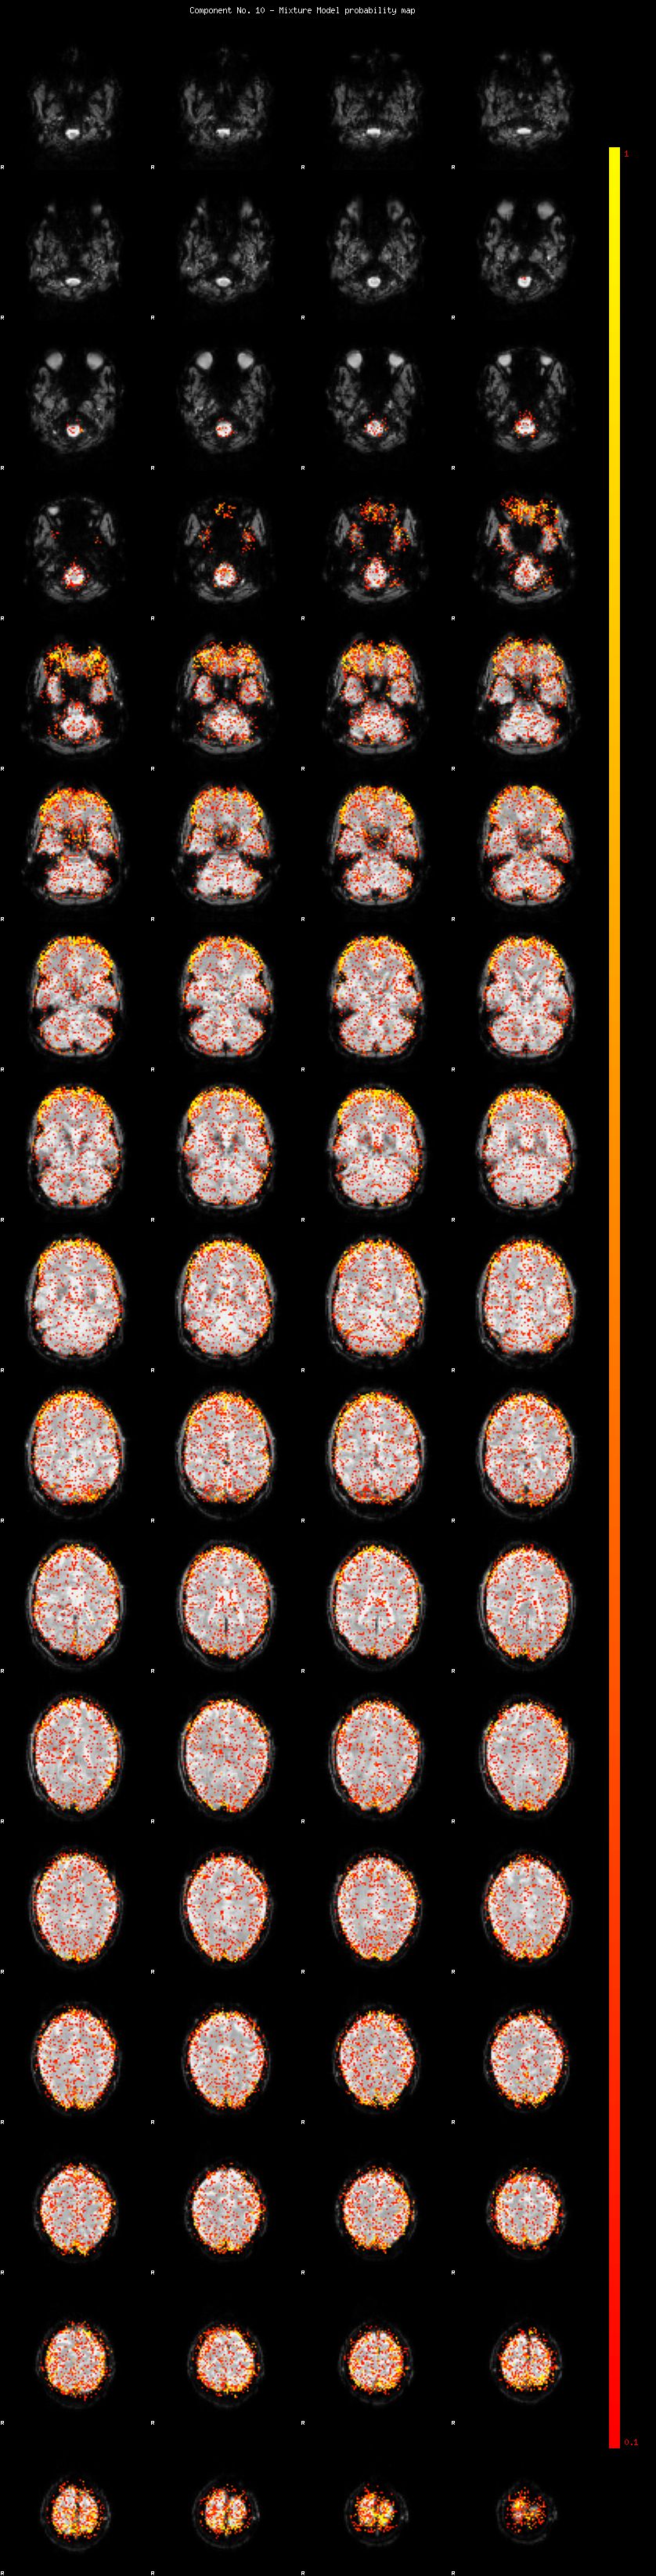

IC_10 Mixture Model fit

Means : -0.000000 2.494467 -2.609873

Vars : 1.000000 1.931745 1.395445

Prop. : 0.897475 0.063250 0.039275